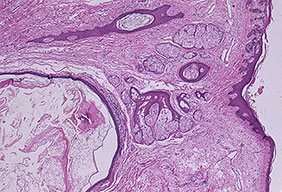

Acne vulgaris erythematous papule =العد الشائع